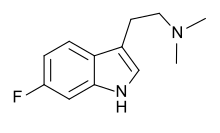

| 6-Fluoro-DMT | artificial | 6-F | CH3 | CH3 | 6-fluoro-N,N-dimethyltryptamine | 1511-31-5 |